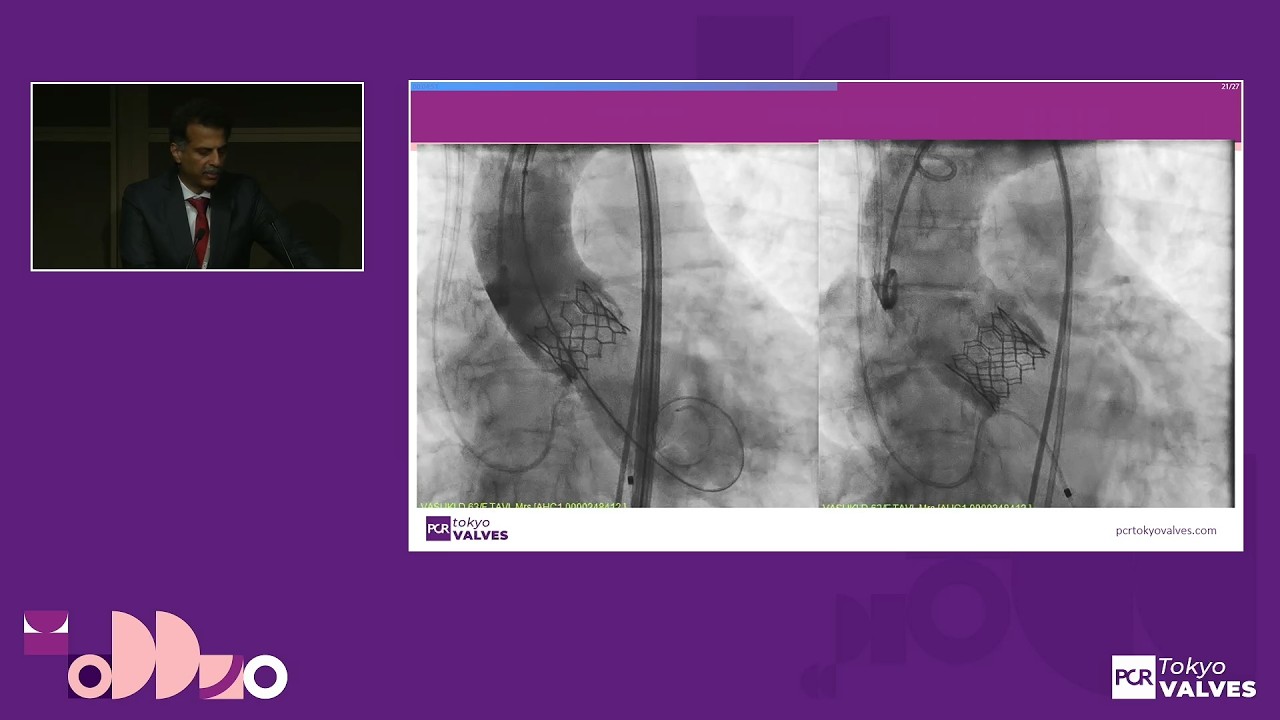

Overcoming complexity in TAVI: a patient-centered approach - PCR Webinar

Watch this on-demand webinar to explore the different sources of complexity in TAVI. Learn how to adapt your procedural strategy based on pre-procedural imaging findings, and discover best practices for the management of patients with heart failure undergoing TAVI, and much more!

00:35:34 – Case 2 – Transfemoral TAVI in complex anatomy: strategy, technique, and hemodynamic outcomes